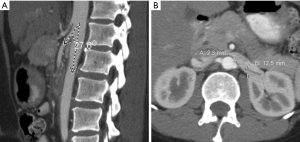

Cross-sectional imaging with CT and MRI relies on vessel diameter and, to a lesser extent, SMA angle to identify pathologic narrowing of the LRV. A normal aorta-to-SMA angle is between 45 and 90 degrees. An angle of 35 degrees in sagittal dimension suggests NCS (37) (Figure 5A). In the axial plane, a characteristic “beak” sign with abrupt narrowing of the LRV at the SMA is reported to have a sensitivity of 91.7% and specificity of 88.9% (38). As normal absolute values vary by patient, studies have focused on the ratio of diameters of the LRV at the renal hilum as compared to those at the narrowed AM segment. On CT, a hilar-to-AM diameter ratio of ≥4.9 has a 66.7% sensitivity and 100% specificity for NCS (Figure 5B) (2). A separate study demonstrated a 91% sensitivity and 91% specificity for NCS with a “compression ratio” of 2.25, which was described as adequate to raise suspicion for the disease, in the context of symptoms (39). Predictably, higher compression ratios were associated with more symptoms.